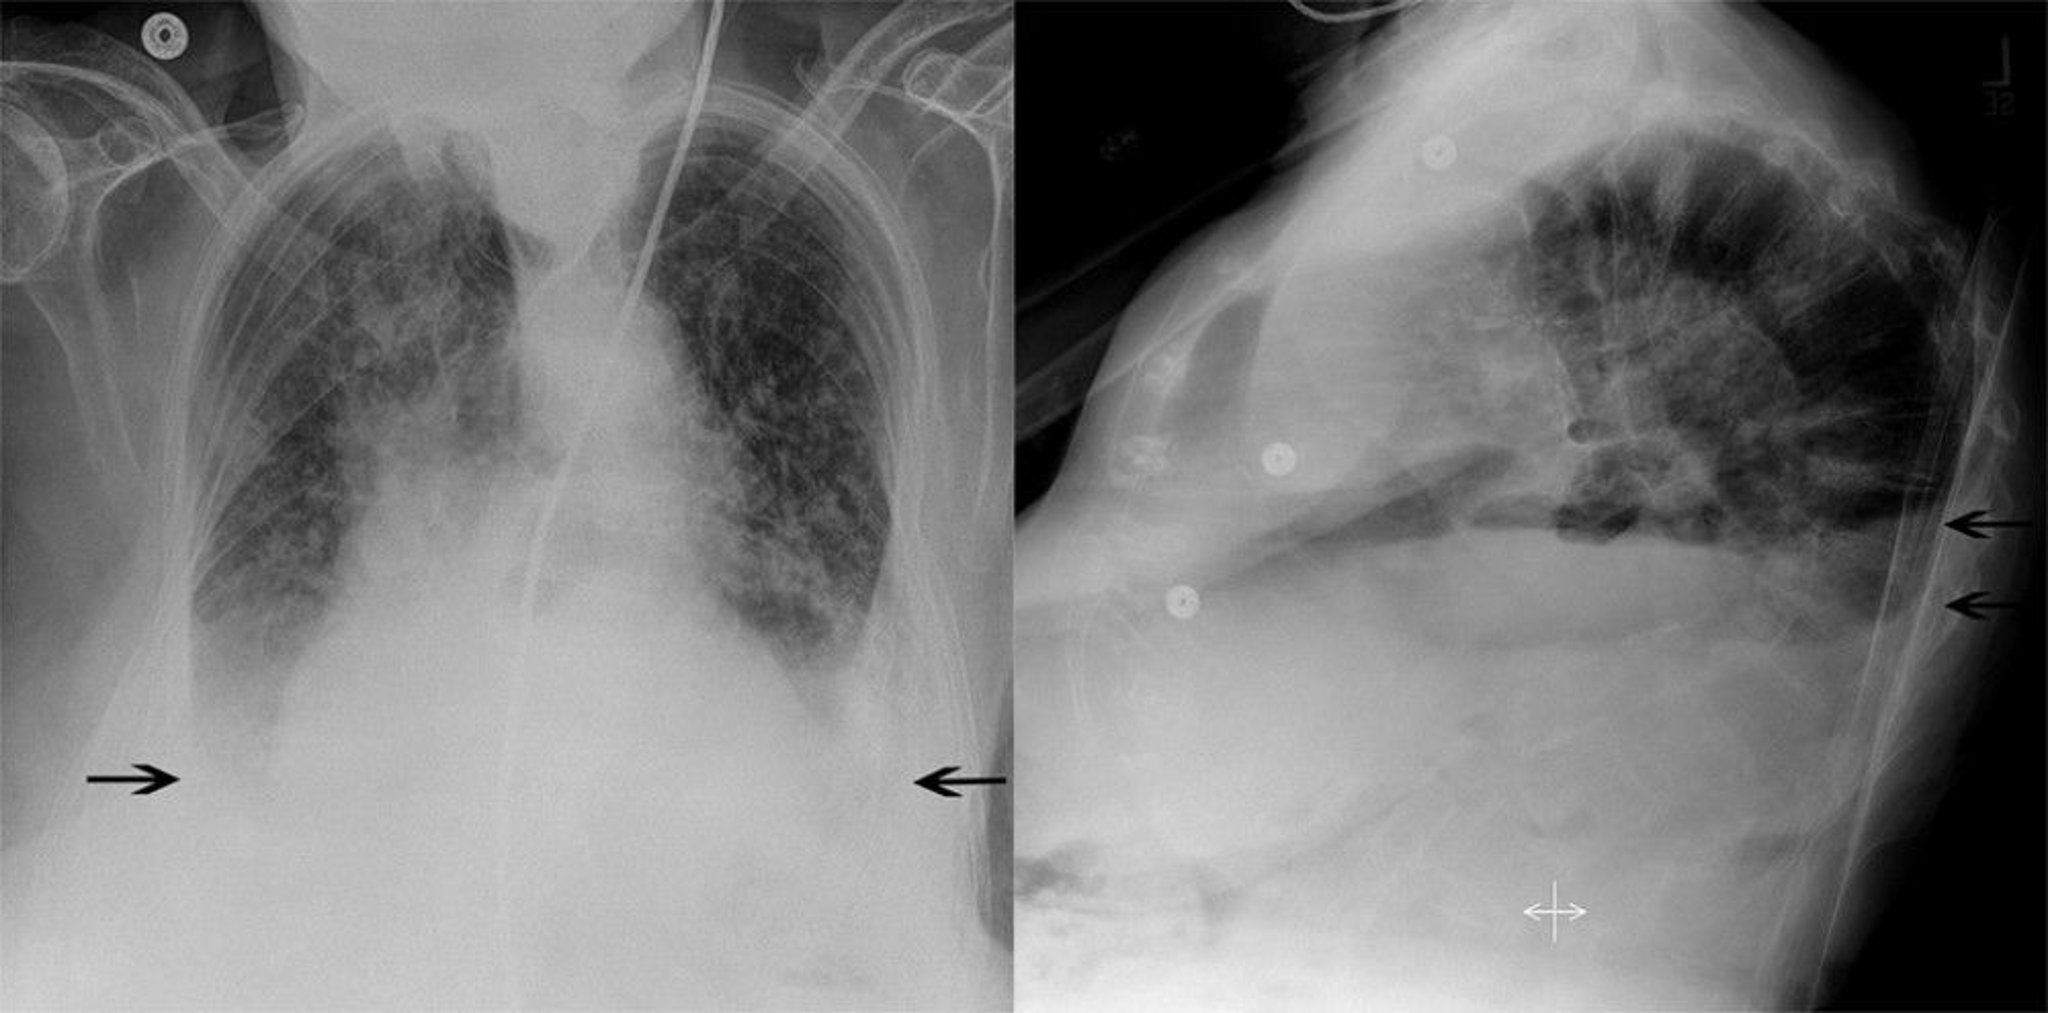

Chest Radiograph of a Patient with Pulmonary Edema and Bilateral Pleural Effusions

This patient has bilateral patchy interstitial infiltrates characteristic of pulmonary edema, as well as bilateral pleural effusions (arrows). The normally sharp costophrenic angles are obscured by fluid.